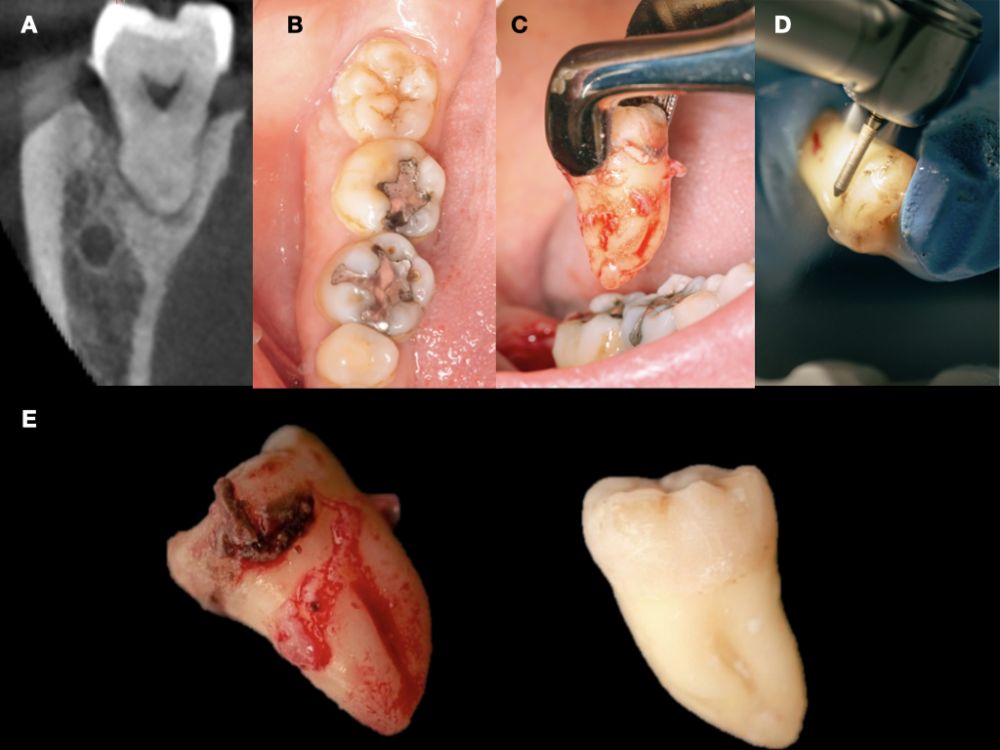

Se planificó la exodoncia del 4.8 para utilizarlo como diente donante, para lo que se firmó previamente el consentimiento informado. Se realizó un bloqueo anestésico mediante articaína (Inibsa®, Barcelona, España) al 4% con adrenalina 1:100.000 del nervio dentario inferior, del nervio lingual y, por último, del nervio bucal. Al ser un diente sin procesos infecciosos asociados, únicamente se eliminó del diente el cálculo mediante instrumental ultrasónico y se realizó la extracción de la forma más atraumática posible. Se pulió la superficie radicular con fresas de diamante de turbina con abundante irrigación, eliminando de esta forma el ligamento periodontal (Figura 3).

Se registró el peso del diente una vez limpio en una balanza de precisión (Ohaus® YA 102, YA Gold Series, Nueva Jersey, EEUU) registrando 2,1 g de peso, y se cortó el diente en fragmentos ≤ 5 mm, colocándose secos dentro del molino del dispositivo Tooth Transformer® (S.R.L, Milan, Italia), tal y como indica el fabricante. Una vez introducido se colocó dentro del dispositivo y se añadió el recipiente con los líquidos, para desmineralizar el diente liberando BMP-2 y colágeno tipo 1, eliminando cualquier tipo de toxicidad residual. Cuando se insertaron todos los componentes la cubierta de la máquina se cerró y, presionando el botón de activación se inició el proceso hasta comprobar el molido de los fragmentos y el tamaño adecuado de partícula, gracias al tamiz que el recipiente recolector posee (400-800µm). En un plazo de 25 minutos se preparó el injerto de diente autólogo y se volvió a pesar en la balanza de precisión, registrando 2,6 g de peso (Figura 4).